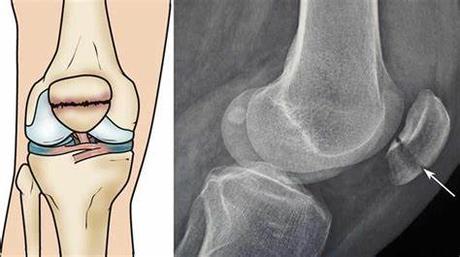

X-rays

These are the most common and basic tests that show the bone structure and the fracture pattern.

X-rays can help to determine the type and severity of the fracture and the alignment of the bone fragments.

The diagnosis of a patella fracture is based on the history of the injury, the physical examination of the knee, and the imaging tests.

The doctor will then examine the knee and check for signs of fracture, such as tenderness, swelling, deformity, and movement.